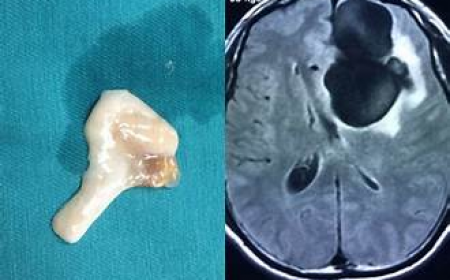

SÁN TRONG NÃO GÂY RA CÁC TRIỆU CHỨNG NHƯ TÂM THẦN

Dấu Hiệu Nhận Biết Sán Lên Não